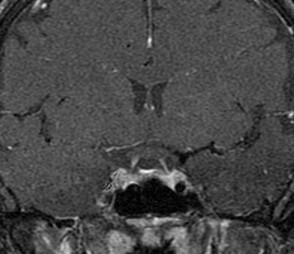

Fused hemispheres, absent or hypoplastic vermis, and superior cerebellar peduncles

Needs to have fusion of the dentate nuclei

Assn: hydrocephalus, limbic anomalies, cortical malformations, absent septum pellucidum, multiples suture synostosis